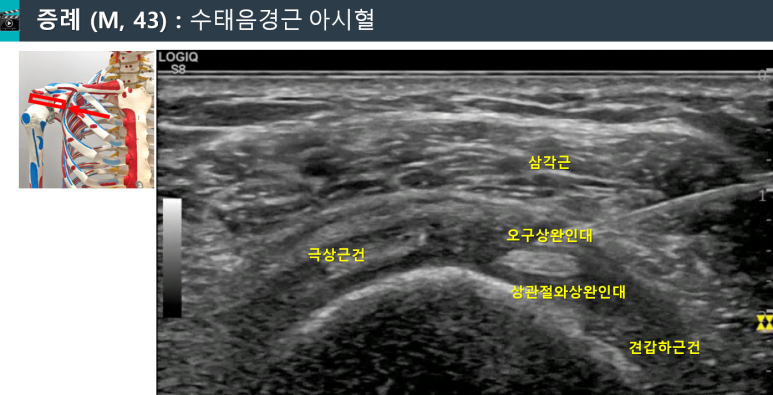

혈 자리의 구조를 보면

회전근개 간격(Rotator interval)에해당하는 곳입니다.

상완이두근 장두 힘줄 주변을

오구상완인대(CHL),상관절와상완인대(SGHL)가둘러싸고 있죠.

위 경혈 초음파 이미지는

교통사고 후 오십견으로

화곡동에서 오신

40대 환자분입니다.

문제가 있는 혈자리를 찾아

정확한 깊이에 시술합니다.